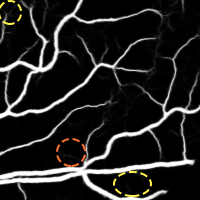

4.2 Validation of the Stationary Wavelet Transform

Having analyzed our Base System, we evaluate the effects of incorporating the SWT into it. The results of each variant are shown in Table 4, while the probabilistic predictions can be seen in Fig. 5. The patches coming from the SWT were concatenated in the input, by varying the total number of input channels. We resorted only to detail coefficients since the goal was to enhance image transitions. We started by concatenating the detail coefficients of the first level in the initial green channel input – BS + . Then, we added those of the second level – BS + + . Finally, only the latter were kept – BS + .

Analyzing the results of the tests performed, we notice that all the alternative strategies improved the performance of the Base System, in terms of Acc and AUC. This means that the use of features based on the wavelet decomposition, whose effectiveness for vessel segmentation is well-known (Soares et al.,, 2006; Zhang et al.,, 2017), is also beneficial when combined with a deep learning methodology. In particular, we see that the first level SWT coefficients used on BS + were less effective than those of the second level applied on BS + . The first level translates spectral information of higher frequencies; this seems to have induced more false positives, as can be seen in Fig. 5. On the other hand, the second level SWT coefficients introduced statistically significant differences to the Base System, in both Acc and AUC, which seems to reinforce the idea that even deep learning methods can benefit from domain knowledge. In fact, they allowed to reduce the combination of false positives and false negatives as we can see in Fig. 5 as well. From now on, we will refer to the best model (BS + ) as Proposed.